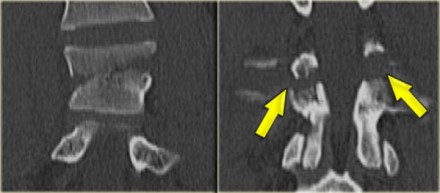

Chance fracture (2)

On the left another example of a Chance fracture.

Chance fracture (3)

On the left a Chance variant.

This is a pure ligamentous injury, which is analogous to bilateral interfacet dislocation, which is also a pure ligamentous injury.

There is rupture of the interspinous ligament, dislocation of the facet joints and a horizontal rupture of the disc.

Pure ligamentous and combined osseous / ligamentous variants have an increased risk of instability compared to the osseus type.

Always look for a split of the posterior elements, disc widening or widening of the spinous processes and facets.